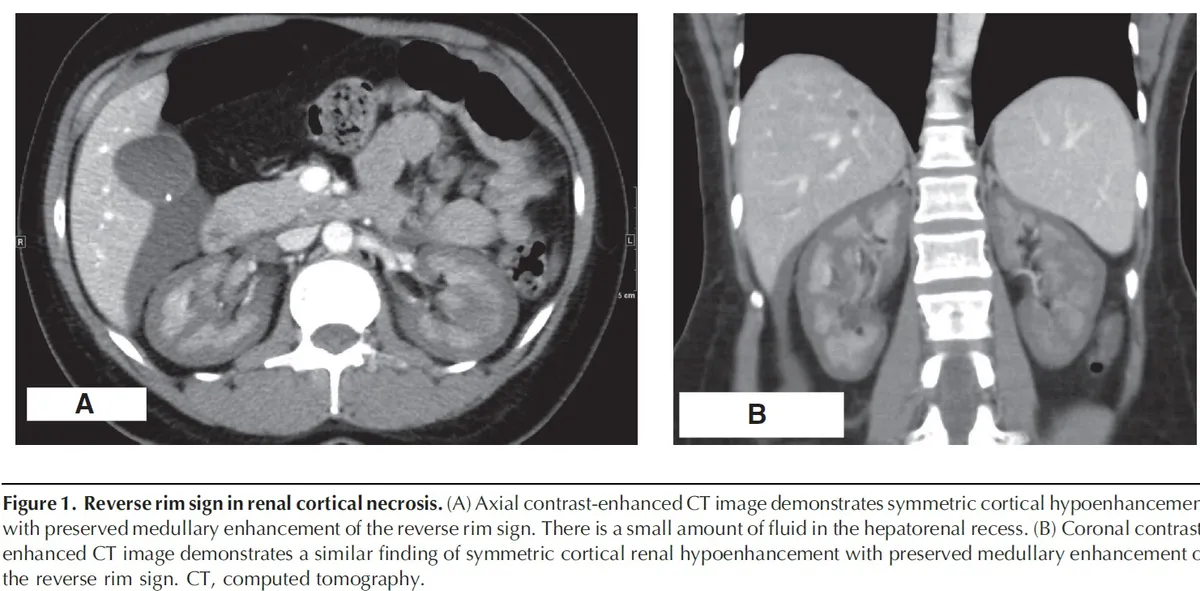

IRA em Mulher Jovem Após Curetagem